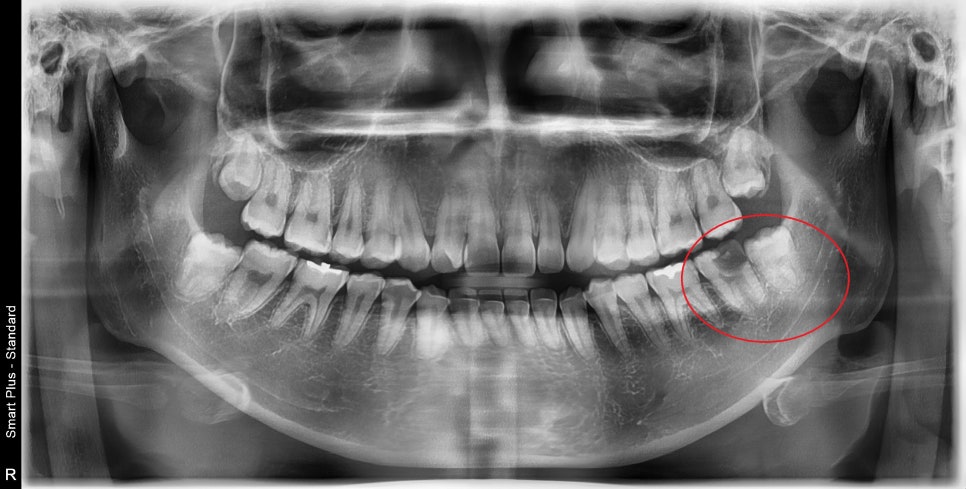

음식 먹다가 치아가 부려졌어요.

좌측 아래의 두번째 큰 어금니입니다.

첫 번째는 신경치료

두 번째는 보철치료 전 사랑니 발치가 필요합니다.

사진으로만 보아도

이미 충치가 진행이 신경까지 진행된 상태이며

약해진 치아는 쉽게 부서지고, 깨지는데

그 공간으로 잇몸이 차오른 것을 볼 수 있습니다.